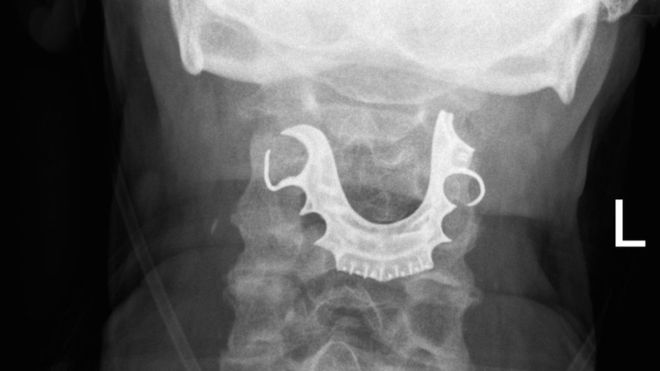

Cuando el hombre regresó nuevamente dos días después, los médicos revisaron su garganta y fue entonces que encontraron un objeto semicircular sobre sus cuerdas vocales. Y todo empezó a cobrar sentido cuando el hombre les contó que había perdido su dentadura postiza durante su operación. Aunque el caso tuvo lugar en 2008, se conoció esta semana tras la publicación de un artículo en la revista BMJ Case Reports, en la que los autores recomiendan que se extraigan los dientes postizos antes de la anestesia general.

Una vez que que le hallaron el objeto en la laringe, ocho días después de la primera operación, el paciente tuvo que ser intervenido nuevamente para remover la dentadura postiza de su cuerpo. Cuando los cirujanos cauterizaron la herida en su garganta, había perdido tanta sangre que necesitó una transfusión.